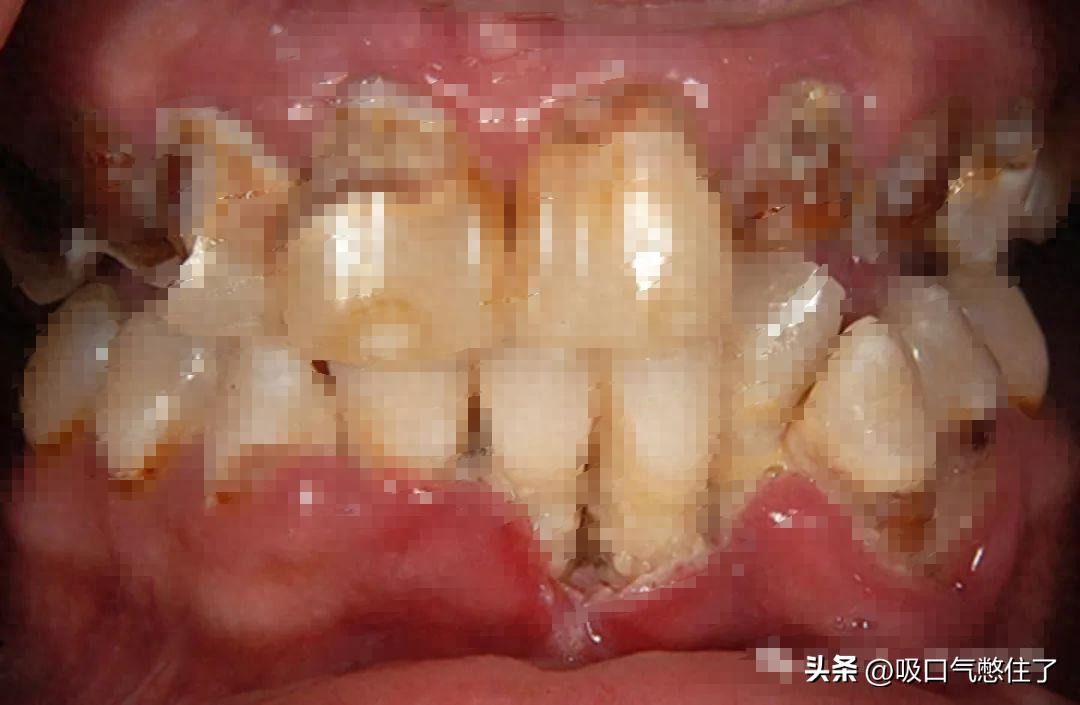

众所周知,长期吸毒会对人体造成的不可磨灭的伤害,其中,冰毒对口腔的伤害巨大,吸食冰毒成瘾的人牙齿表面牙釉质受到腐蚀,呈现黄褐色,我们称之为 “冰毒嘴”。

冰毒的主要成分甲基苯丙胺呈酸性,会对牙齿造成腐蚀,导致牙齿外层会出现特有的腐蚀症状。另一方面,吸食冰毒后唾液分泌会减少,出现口干,吸毒者口腔内的酸性物质无法中和,进而损伤口腔。

这图有毒,看得心里瘆得慌,打马赛克了

“冰毒嘴” 的特点是严重的蛀牙和牙龈疾病,经常导致牙齿变黑、变色、腐烂、碎裂和脱落。其口腔全景图像表现如下: